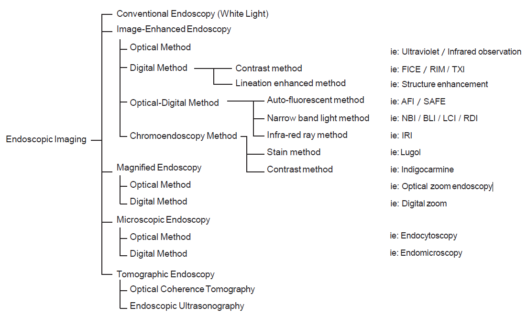

According to the morphology of the anatomical components, the MV and MS patterns were classified as regular, irregular, or absent (. Fig. 2). In principle, the MV and MS patterns must be determined separately.

DL is defined as the border between the lesion and non-lesion areas, discernible through an abrupt change in MV and/or MS patterns (. Fig. 2).

The working group members carried out a systematic review of the English literature to determine widely accepted diagnostic systems. Consequently, the best-accepted diagnostic system was proven to be the VS classification system. Based on this system, MESDA-G was constructed using an evidence-based approach (. Figs. 3, 4, 5, and 6) [2]. First, lesions suspicious for EGC should be detected by careful inspection using conventional white-light endoscopy. Subsequently, magnified observations should be performed. Owing to the high sensitivity of the demarcation line [8], if it is absent, the suspicious lesion is diagnosed as noncancerous (. Fig. 4a, b). However, if the demarcation line is present, further assessment is required to determine the presence of an irregular MV or MS pattern. If an irregular MV and/or MS pattern is detected, the suspicious lesion is diagnosed as cancerous (. Fig. 6a, b) [1, 5, 6, 8]. If both the irregular MV and MS patterns are absent, the tumor is diagnosed as noncancerous (. Fig. 5a, b) [1, 5, 6, 8].